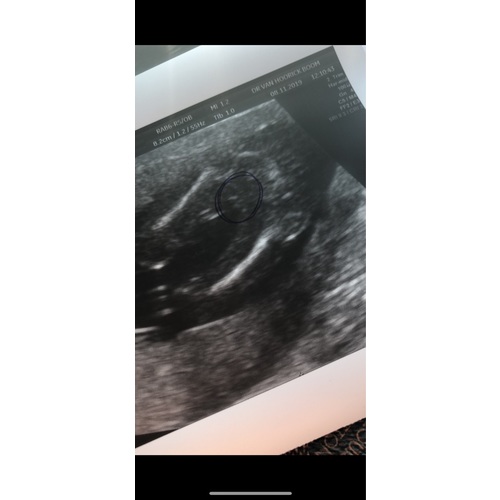

Lijkt mij wel echt een jongen! Ben geen ervaringsdeskundige natuurlijk, maar lijkt redelijk op hoe onze geslachtsecho was 😏

Lijkt inderdaad op een jongen. Zie onze echo wij krijgen ook een jongen. Die van ons is wel stuk duidelijk vindt ik zelf. Bij een meisje zie je een streepje en geen uitsteeksels

Wij hebben ook een geslachtsecho bij babyvision in Delft gedaan. Ook een jongentje, klopte zeker weten (meerdere keren bevestigd daarna, ben nu 40 weken). Echo lijkt ook op die van mij. Denk wel dat het klopt.

Met hoeveel weken heb je deze echo laten doen? Het lijkt namelijk wel veel op de echo die wij hadden...

Duidelijk een jongen. Ik krijg een meisje en daarbij zag je duidelijk de hamburger, hier zie je echt balletjes.